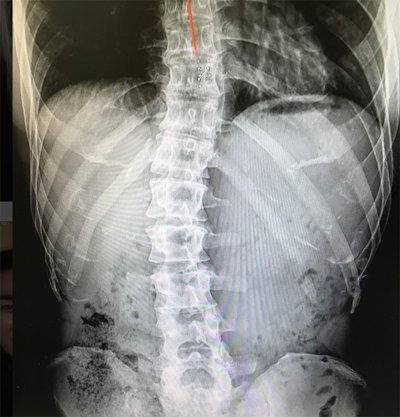

진단은 어떻게 이루어질까?

X-ray 또는 CT: 척추 정렬과 골격의 이상 여부를 확인합니다.